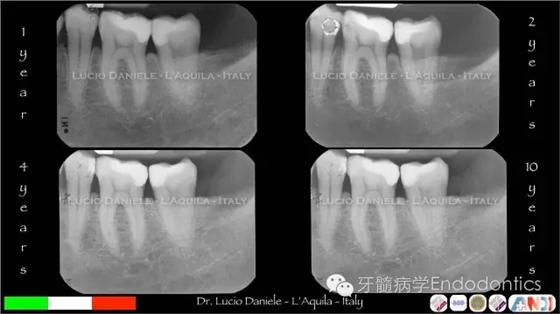

圖16.隨訪1年、2年、4年、10年